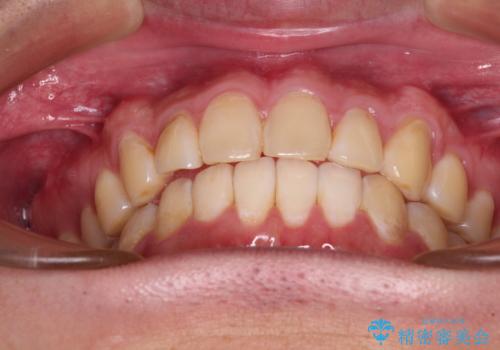

- 9ヶ月

しかし、費用面や期間で悩んでいらっしゃったため、左側臼歯の問題は解決せずに前歯のデコボコのみを改善するシミュレーションを作成し、治療を行うこととしました。

写真より左側臼歯の咬合がタイトではないことが分かりますが、こちらは保定期間に徐々に咬合させていくこととしました。